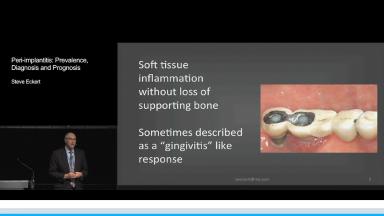

However, observations of soft and hard tissue changes adjacent to dental implants have been made. Clinicians have suggested that these observations are similar to those associated with periodontal disease.

Despite these observations there are many who believe that peri-implantitis can not be compared to a "periodontal" disease adjacent to a dental implant. In fact, review of current literature that addresses this disease process would suggest that the management of this problem using similar technology for the management of periodontal disease may not be successful with implants.